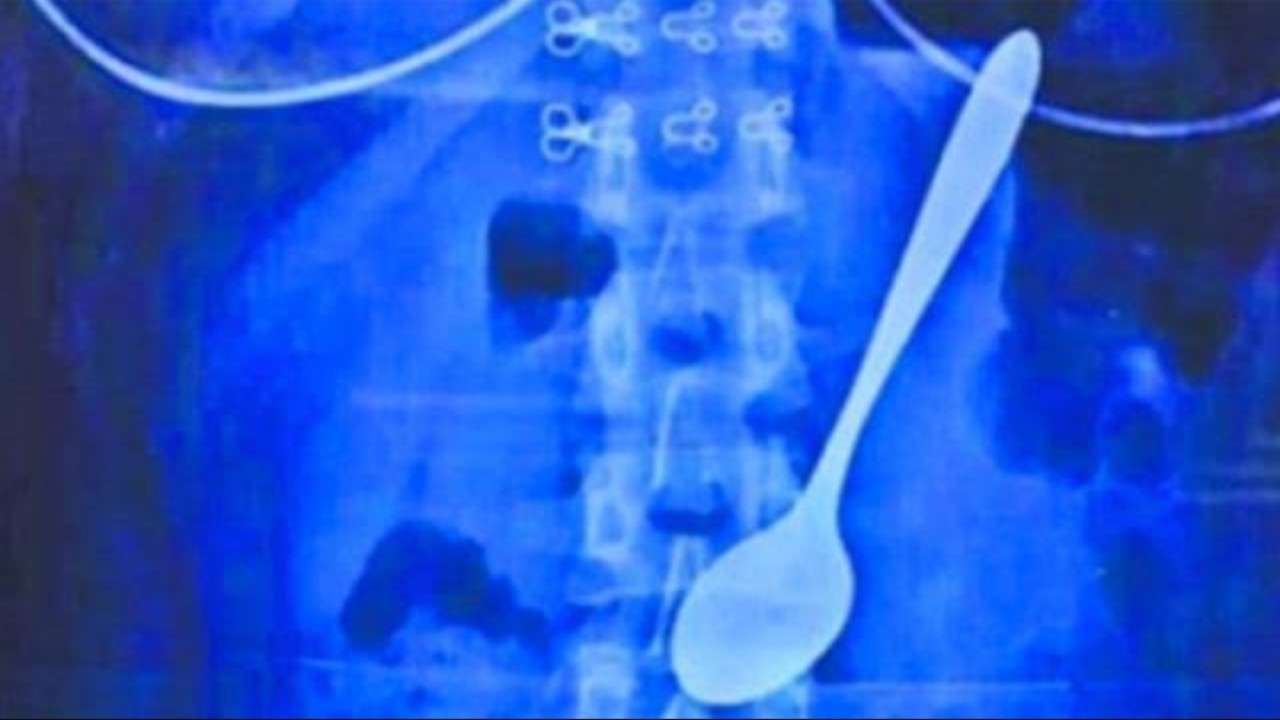

"Vijay dibawa ke rumah sakit sekitar 15 hari yang lalu, dan dari pemeriksaan X-ray, kami temukan benda logam di usus besarnya. Ketika saya menanyakan hal ini ke pasien, Vijay mengaku bahwa dia dipaksa untuk menelan sendok-sendok tersebut. Akhirnya kami lakukan tindakan operasi selama dua jam, tapi kami belum pernah melakukan operasi seperti ini sebelumnya," tutur Dokter Rakesh.

Bentuk sendoknya juga bukan sendok utuh. Melainkan Vijay harus mematahkan kepala sendok, dan yang dimakan hanya bagian gagang sendoknya saja.

Untungnya nyawa Vijay masih bisa tertolong. Ia kini masih berada di ICU, dan dalam proses pemulihan usai 63 sendok dikeluarkan daari perutnya.